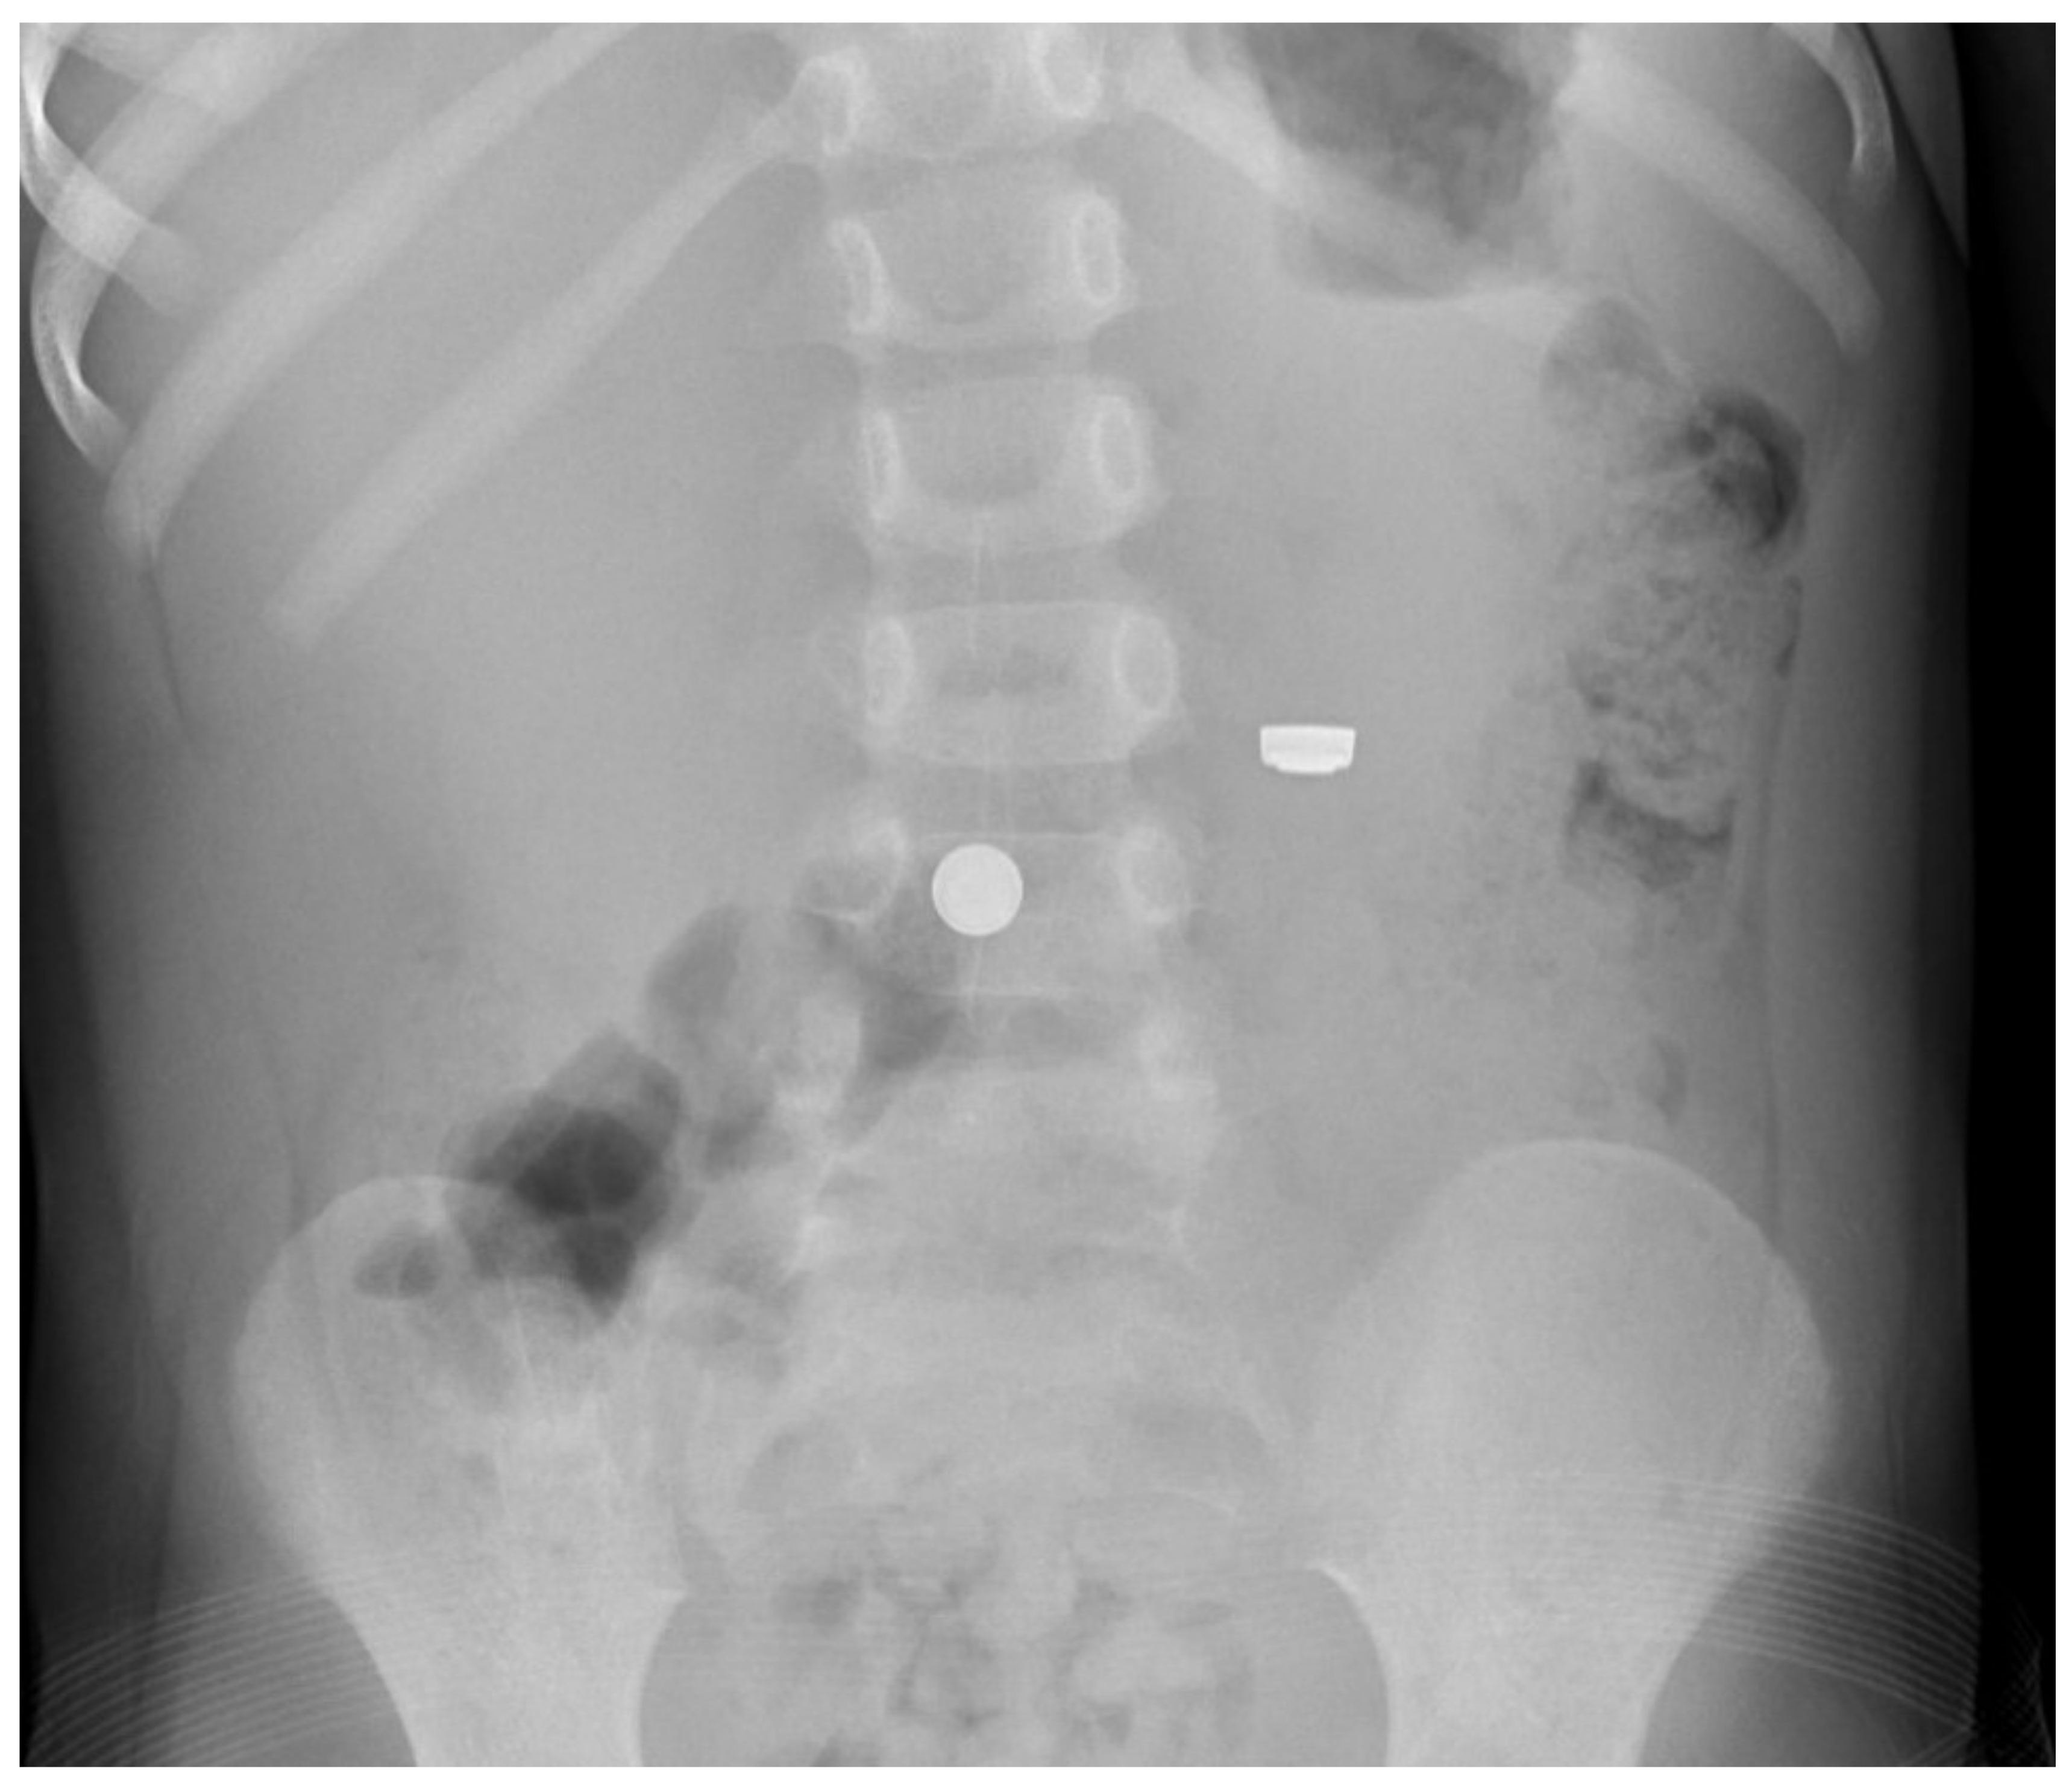

Figure 4.

Abdominal radiograph of a child showing swallowed button batteries in two different orientations.

Imaging of a child whose symptoms suggest abdominal pathology, or who is suspected of ingesting small, powerful magnets [18], should include the abdomen. While dedicated chest (and, if necessary, abdominal) radiographs are generally preferable, a single “babygram” that includes both areas is sufficient to screen for the presence of easily-identified metallic foreign bodies in the chest or abdomen of small children; additional, follow-up imaging may be necessary for those revealing a foreign body.